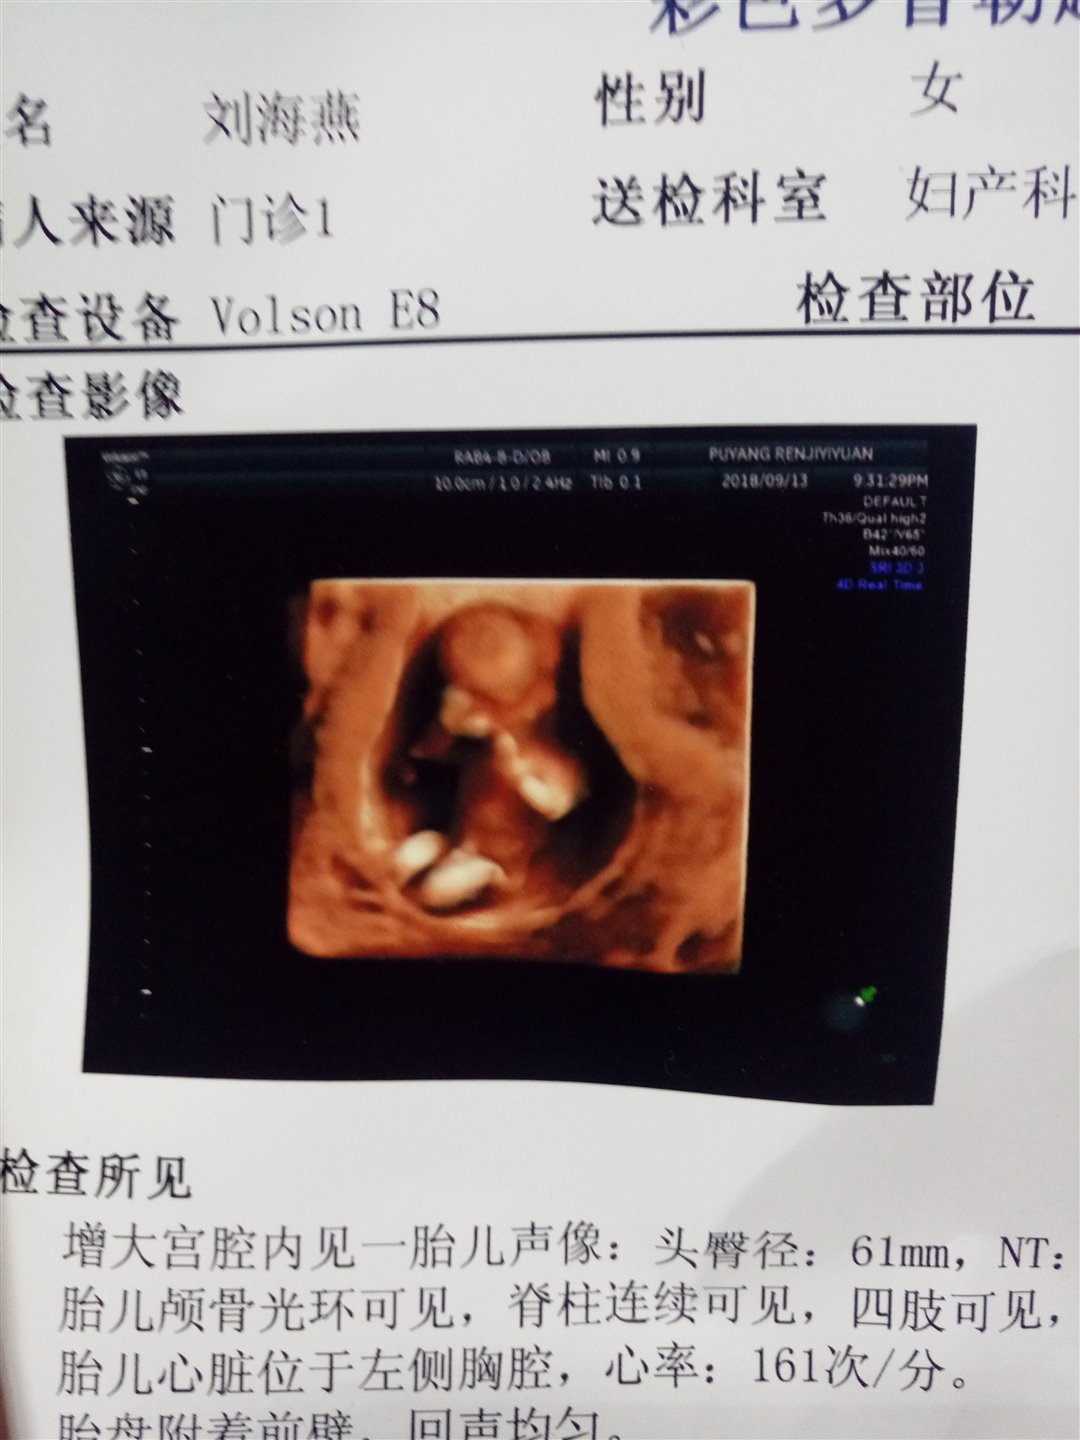

孕12周+3天

还有三天就要去NT了…希望能像您一样顺利通过…